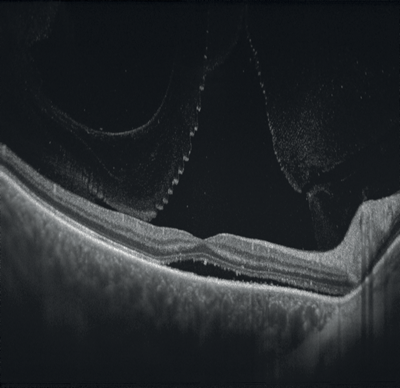

Figures 1-4: Swept-source OCT (DRI OCT-1 Triton, Topcon) images of healthy eyes that clearly delineate features in the vitreous, including area of Martegiani, bursa premacularis and posterior hyaloid, right through to the sclera, in the same single scan.

Topcon’s newly-introduced swept-source DRI OCT Triton can capture 256 B-scans in less than three seconds, with high speed scanning of 100,000 A-scans per second and a 1050nm wavelength which can penetrate easily through cataracts and haemorrhages. It features widefield 12 by 9mm scan screens for both glaucoma and macular pathology in one scan, with consistent signal strength from cortical vitreous to the sclera with an average of up to 128 times, automatic detection of seven retinal layers, as well as 2.6 micron digital resolution. The DRI OCT Triton has a built-in high resolution colour fundus camera, fundus guided acquisition (SmarTrack) and the option of an anterior imaging module. The Triton Plus also features fundus autofluorescence and fluorescein angiography, and an OCT angiography module is currently under development.